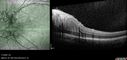

Albinism and Renal failure - Possible Hermansky-Pudlak Syndrome72 views65 year old female with foveal hypoplasia and renal failure since age 18. VA 20/40 OD, 20/63 OSDec 21, 2024

Albinism and Renal failure - Possible Hermansky-Pudlak Syndrome66 views65 year old female with foveal hypoplasia and renal failure since age 18. VA 20/40 OD, 20/63 OSDec 21, 2024

Albinism and Renal failure - Possible Hermansky-Pudlak Syndrome73 views65 year old female with foveal hypoplasia and renal failure since age 18. VA 20/40 OD, 20/63 OSDec 21, 2024

Albinism and Renal failure - Possible Hermansky-Pudlak Syndrome83 views65 year old female with foveal hypoplasia and renal failure since age 18. VA 20/40 OD, 20/63 OSDec 21, 2024

Albinism and Renal failure - Possible Hermansky-Pudlak Syndrome79 views65 year old female with foveal hypoplasia and renal failure since age 18. VA 20/40 OD, 20/63 OSDec 21, 2024

Albinism and Renal failure - Possible Hermansky-Pudlak Syndrome54 views65 year old female with foveal hypoplasia and renal failure since age 18. VA 20/40 OD, 20/63 OSDec 21, 2024

Albinism and Renal failure - Possible Hermansky-Pudlak Syndrome71 views65 year old female with foveal hypoplasia and renal failure since age 18. VA 20/40 OD, 20/63 OSDec 21, 2024